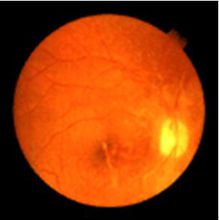

2.眼底改變

早期可見黃斑部呈顆粒狀色素脫失 中心凹光反射彌散,黃斑區呈錫箔樣。有的雙眼黃斑部出現水腫及滲出物、色素斑點,中心凹反光彌散。病情逐漸發展,兩眼黃斑部表現為環形或卵圓形邊界清楚的病變區。該區色素上皮及脈絡膜毛細血管消失(圖1) 脈絡膜大血管呈白線狀,這種病變一般可以發展到50歲以上,病變區內脈絡膜的血管亦可閉塞。隨著病程發展,黃斑部漸形成類圓形鏡界清楚的鑿孔樣萎縮區,雙眼基本對稱,呈灰綠色,有青銅樣反光,其中摻雜有棕黑色及黃白色小點,其內可見脈絡膜血管及白色鞏膜背景。所有病變都局限於黃斑區或黃斑旁區,從不累及及中央區以外的區域。及無異常。